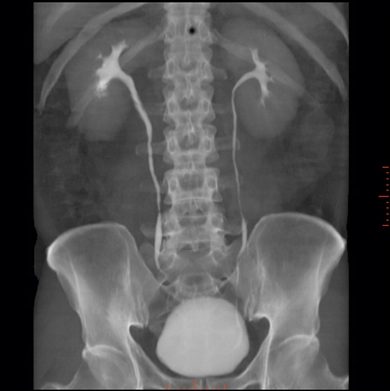

Экскреторная урография почек

Обнаружить негативные факторы, способные затруднить работу мочеполовой системы, позволяет экскреторная урография. Так называется диагностическая процедура с контрастированием, оценивающая выделительный канал.

Снимки, аналогичные рентгенографии, делаются через определенные промежутки времени, благодаря чему можно проследить функционирование выделительной системы.

Для обычных рентген лучей мочевыводящие пути недоступны. Они расположены слишком глубоко в теле человека, поэтому получить их четкое отображение не удается. Эту проблему с легкостью решает экскреторная урография. На ее снимках отлично визуализируются структуры мочевыводящих путей, обладающих способностью выделять в кровеносную систему контрастное вещество. Оно подсвечивает мочевыводящие пути и позволяет сделать наглядный снимок. На нем будут заметны:

Отслеживание этапов прохождения контрастирующего вещества по выделительной системе позволяет сделать профессиональное заключение о ее состоянии и имеющихся у пациента проблемах со здоровьем.

Перед обследованием пациенту вводится йодосодержащее вещество. Через определенное время, когда оно попадает в выделительную систему, начинают делать снимки. Строгое разделение съемки по времени позволяет увидеть паренхиму почек, чашечно-лоханочную систему, мочеточники, мочевой пузырь и мочеиспускательный канал. При затрудненном оттоке мочи процедура длится около 2 часов, для большинства пациентов ее продолжительность составляет 1 час.